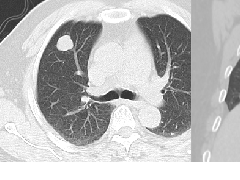

纵隔大细胞神经内分泌癌1例CT影像

纵隔大细胞神经内分泌癌1例CT影像  张力性纵隔气肿影像表现及严重度分级

张力性纵隔气肿影像表现及严重度分级  迅速增大的肺部结节,首先考虑良性,确诊需要肺穿

迅速增大的肺部结节,首先考虑良性,确诊需要肺穿  肺隔离症:易误诊为肺癌的占位性病变,肺穿刺禁忌!

肺隔离症:易误诊为肺癌的占位性病变,肺穿刺禁忌!  肺段与肺内管道应用解剖